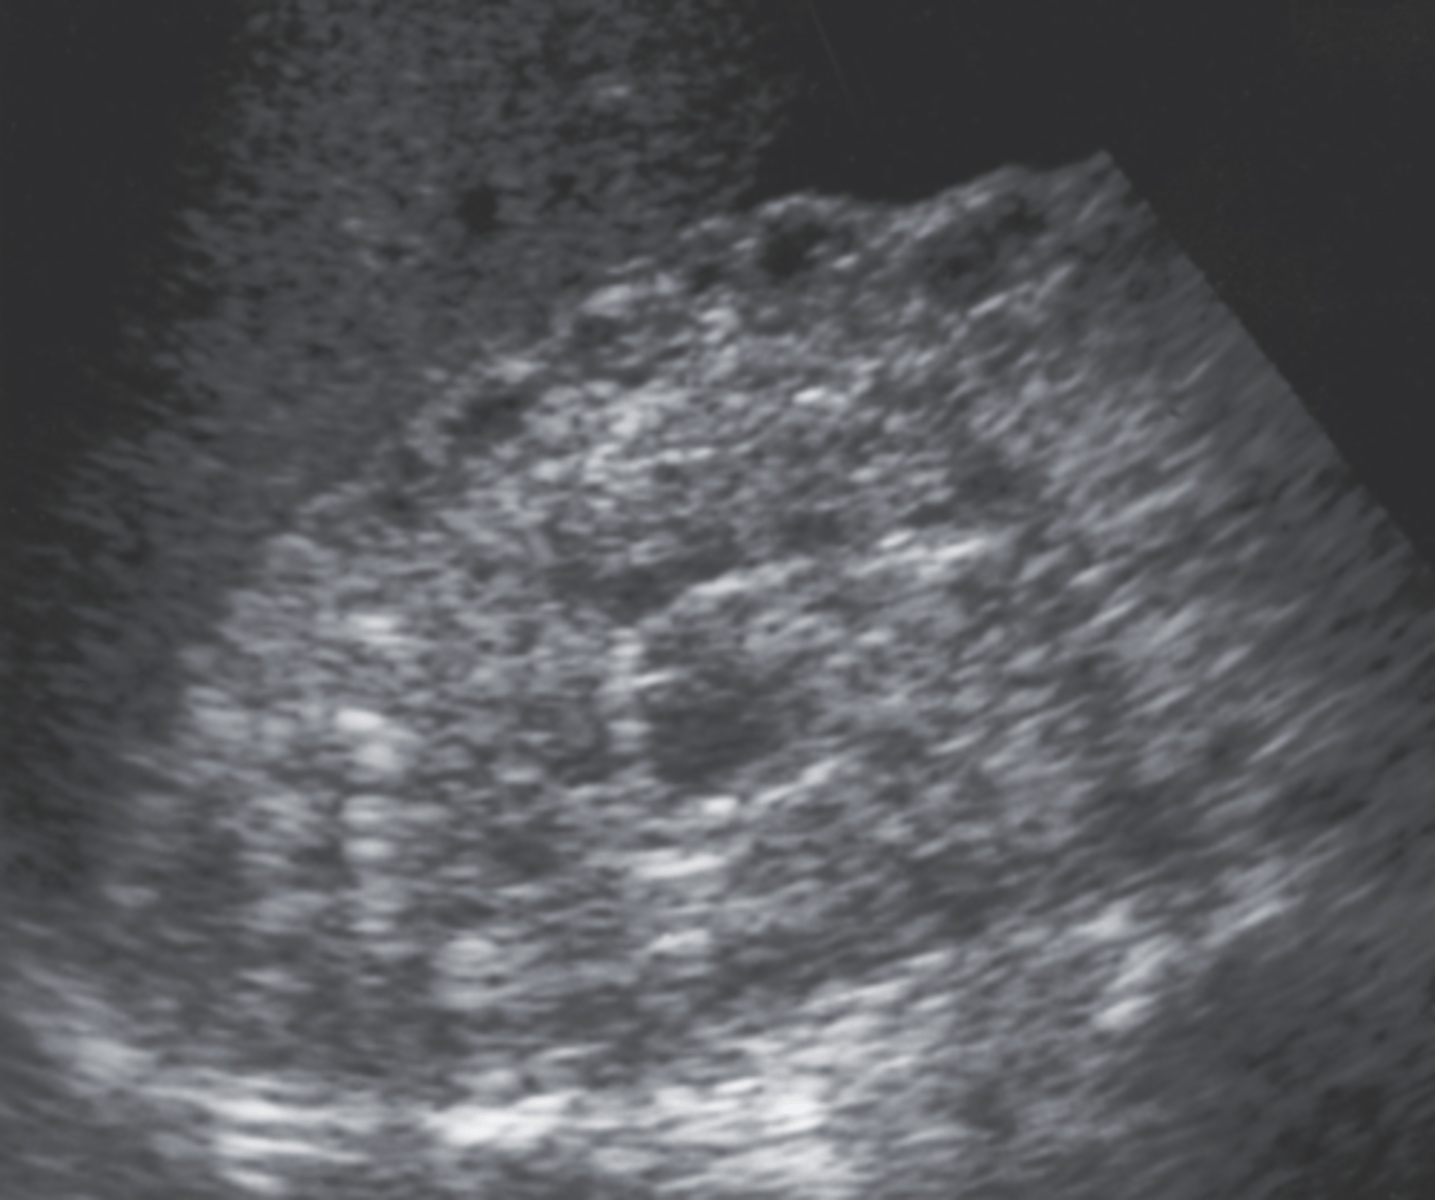

5. The 41-year-old patient in Figure 7-42 had a clinical history that included decreased renal function, urinary tract infections, and a palpable abdominal mass. What is the most likely diagnosis?

a. Acquired renal cystic disease

b. ARPKD

c. MCDK

d. ADPKD

6. Which of the following would be most likely associated with the findings in Figure 7-42?

a. Urinary tract infection